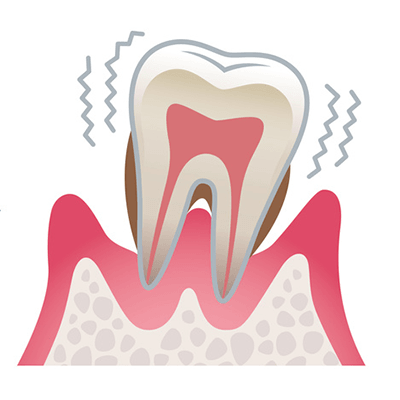

3.重度歯周病

歯を支える顎の骨が大きく溶かされ、歯周ポケットは非常に深くなります。

歯は強くグラつき、歯ぐきから膿が出たり、口臭も強くなります。

最終的には歯が自然に抜け落ちてしまうこともあります。

3.重度歯周病

歯を支える顎の骨が大きく溶かされ、歯周ポケットは非常に深くなります。

歯は強くグラつき、歯ぐきから膿が出たり、口臭も強くなります。

最終的には歯が自然に抜け落ちてしまうこともあります。